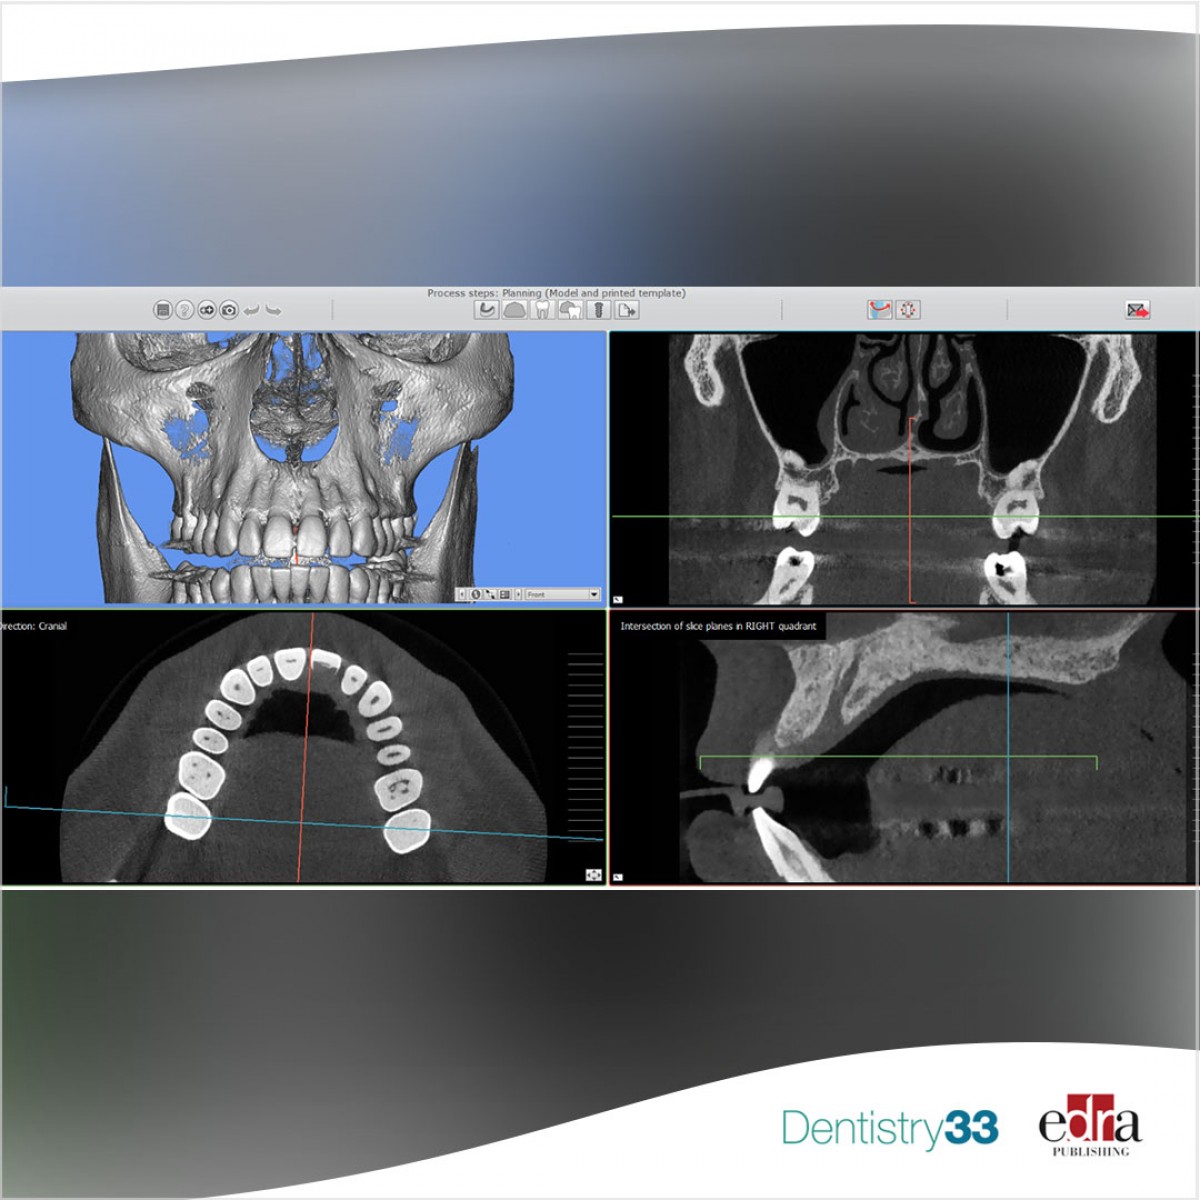

After data collection, a digital application (DSDApp, LLC) was utilized to create a 2D facially driven smile frame which showed the need for surgical crown lengthening to improve the esthetics. Clinicians conducted a cone-beam computed tomography (CBCT) exam and a 3D digital diagnostic wax-up were required for the perio analysis and surgical planning.

The digital procedure allowed the team to create a virtual model of the patient collecting all the anatomical and periodontal information and plan using NemoStudio software (Nemotec, Madrid, Spain), a double guide based on aesthetic and biological requirements. The use of the guide during surgical procedures allowed the team to perform gingivectomy and osteotomy as planned. The inner edge of the guide indicated the new gingival margin, while the outer edge pointed out the height of the bone crest.